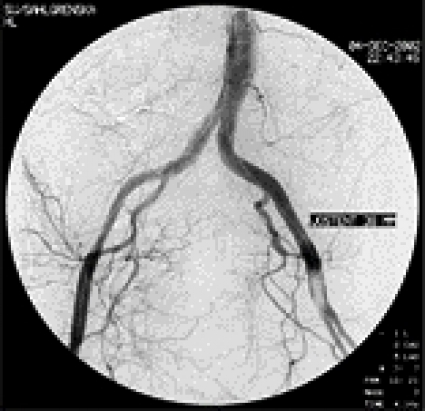

En 5 F införingshylsa infördes i höger femoralartär. Blödningen förmodades härstamma från någon av tarm- eller bäckenkärlen, och initialt gjordes selektiva kateteriseringsförsök. För att påvisa pågående blödning deflaterades aortaballongen från vänster sida. Då profus blödning per rectum åter uppstod utfördes i stället en oselektiv bäckenangiografi, med en kateter placerad distalt i bukaorta. En fistel mellan vänster arteria iliaca externa och rektum påvisades (Figur 2), med en kraftig extravasering av kontrastvätska ut i rektum (Figur 3). En 8 ¥ 30 mm ballongkateter expanderades i arteria iliaca externa över fistelmynningen. Förnyad bäckenangiografi visade upphävd blödning (Figur 4).

Med ledning av angiografin, och en detaljerad information om skadans lokalisation och kärlstorlek, beslutades om endovaskulär behandling. En 38 mm lång stent täckt med dakronväv (Figur 5) expanderades över en 9 ¥ 40 mm ballong på denna plats för att täta fistelavgången. Kontrollangiografi visade täta förhållanden (Figur 6), och patienten blev omgående cirkulatoriskt stabil. Fortsättningen blev odramatisk. Katetrarna avlägsnades och hemostas erhölls i höger ljumske (5 F hål) via perkutant införd kollagenplugg. Det större hålet (18F) i vänster femoralartär krävde dock öppen suturering i lokalanestesi av kärlkirurg. Principiellt kunde slutning ha utförts med perkutan sutureringsteknik.